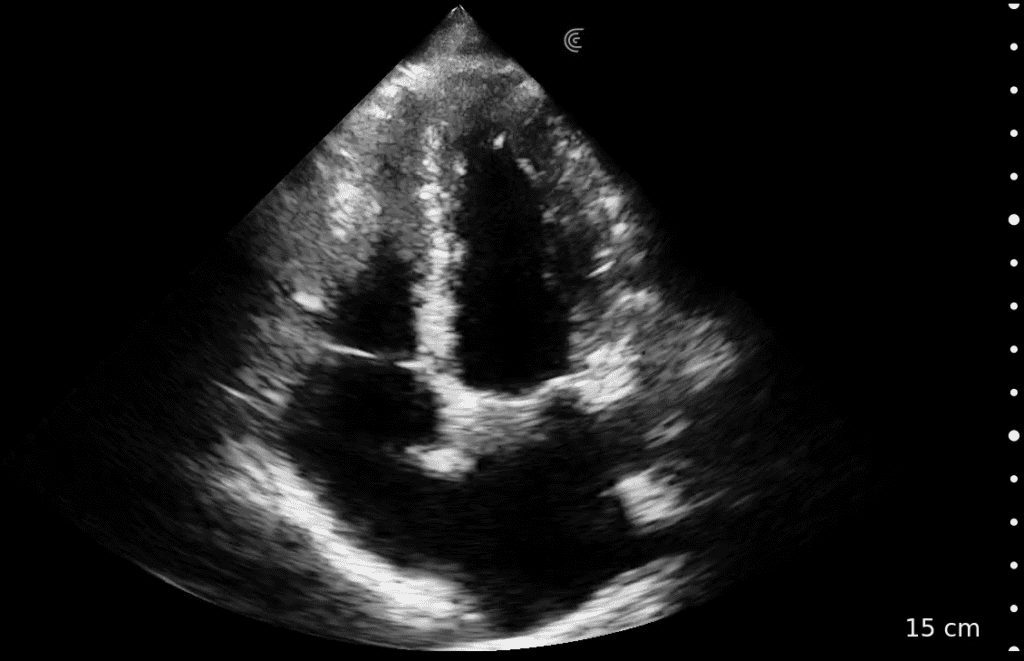

There is no comparison between the sharpness and clearness of the image from the Clarius C3 to the other machines